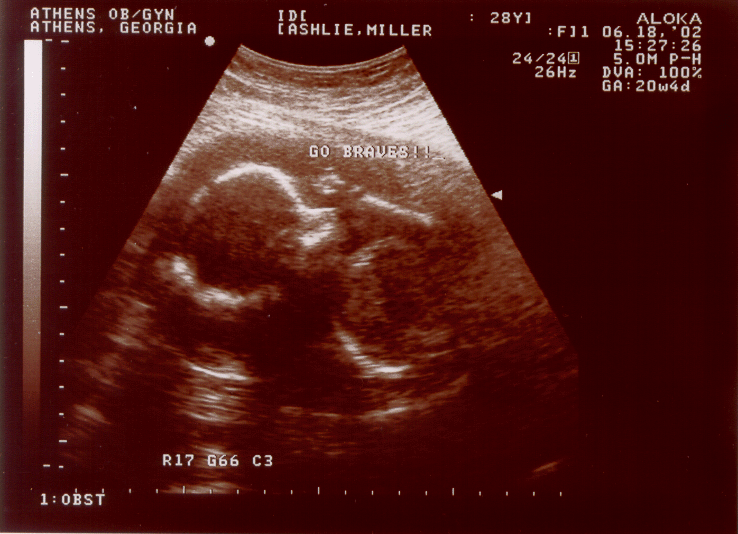

Jack - 20 weeks 4 days